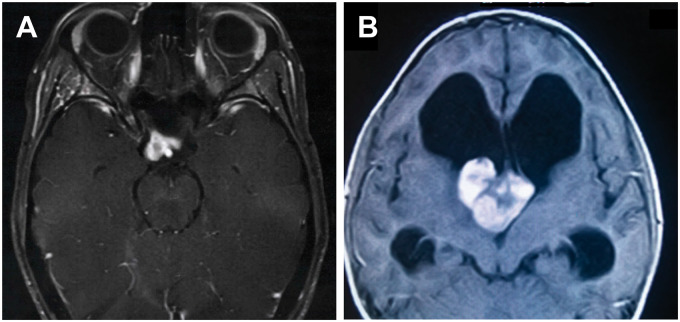

FIGURE 1.

間腦神經(jīng)膠質(zhì)瘤的放射學(xué)特征。(A) T1加權(quán)磁共振成像(MRI)顯示視交叉和右側(cè)視神經(jīng)受累,可見一對比增強(qiáng)的部分囊性腫塊。(B) T1加權(quán)MRI顯示第三腦室前部可見一巨大、分葉狀、對比增強(qiáng)明顯的腫塊。注意側(cè)腦室明顯梗阻性腦積水。